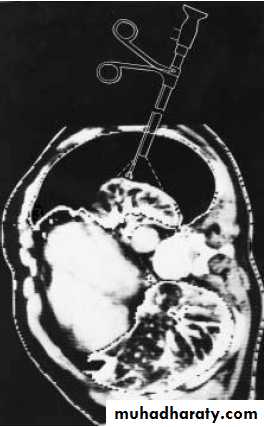

Tension pneumothorax must be treated as a medical emergency .

A large –bore needle should be inserted into the pleural space through the second anterior intercostal space .If large amounts of gas escape from the needle after interior , the diagnosis is confirmed.

The needle should be left in place until a thoracotomy tube can be inserted .